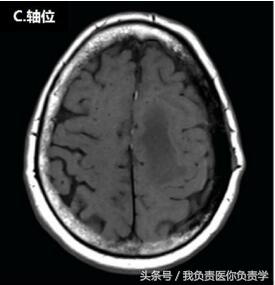

脑MRI显示,患者左侧额-顶部有一较大占位,增强扫描可见强化,从颅内、外延伸至上矢状窦(如图下所示),累及左侧额叶、顶叶和颞骨,左侧硬脑膜增厚。在颅内肿块压迫下,临近部位脑组织表现出血管性水肿。

▲头皮下占位病变。上图可见一较大的颅内外占位性病变,延伸至上矢状窦、大脑、软组织和颅骨。图(A)和图(B)T1增强见左侧硬脑膜增厚;图(C)T1可见脑水肿,图(D)为T2。